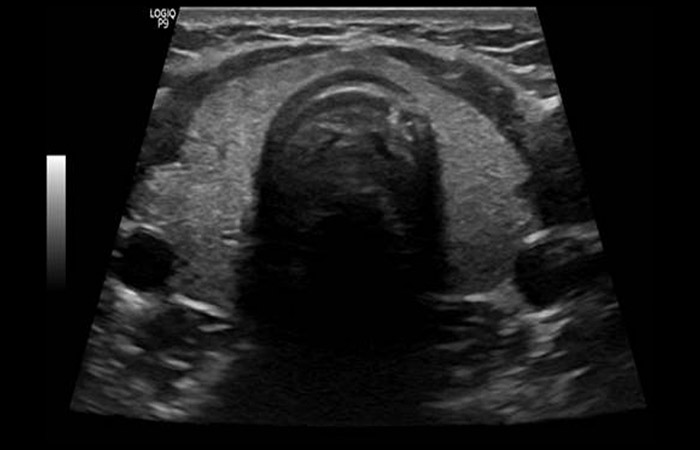

Το υπερηχογράφημα του θυρεοειδούς αποτελεί απεικονιστική εξέταση εκλογής για παθήσεις του θυρεοειδούς και των παραθυρεοειδών αδένων, ενώ είναι χρήσιμο και στην αξιολόγηση της μορφολογίας των τραχηλικών λεμφαδένων καθώς και στον προσδιορισμό της θέσης τους σε περίπτωση παθολογίας.

Με το υπερηχογράφημα, ο θυρεοειδής αδένας ελέγχεται για τις διαστάσεις του, την ομοιογένεια ή μη του παρεγχύματος, την παρουσία όζων καθώς και την αγγείωσή του.

Επίσης συμβάλει στην ανάδειξη τυχόν παθολογίας και στους παραθυρεοειδείς αδένες (παρουσία αδενωμάτων).